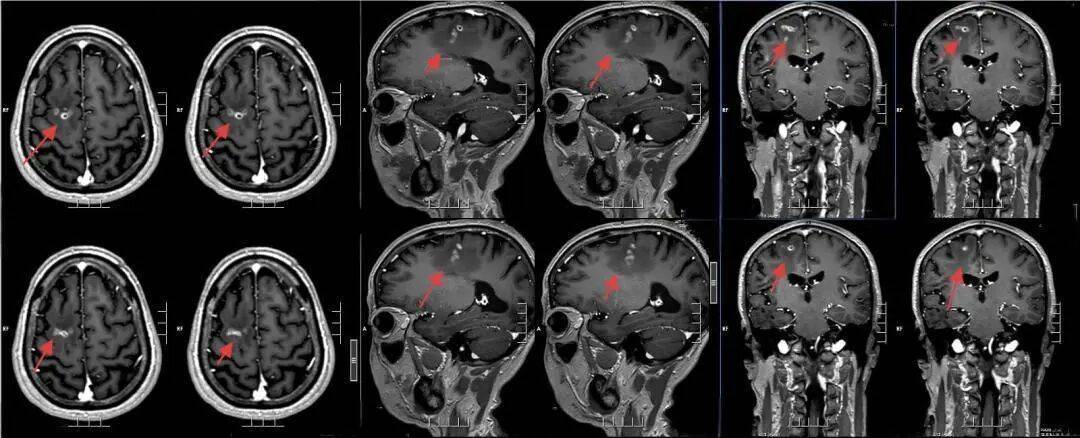

该院神经外二科张旭标副主任医师接诊后,笔据影像恶果,发现其右额叶病变,局部肉芽肿酿成伴周围组织水肿。“这是大脑为了潦倒‘入侵者’筑起沿途‘潦倒墙’,周围的脑组织被刺激得肿胀。”张旭标解说,这些影像特征高度指向脑裂头蚴病。经比对,病灶界限沉着,手术时机老练。

术前影像